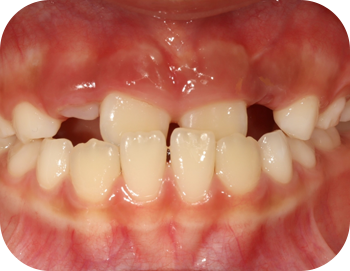

얼굴 골격의 성장에 문제가 있는지를 파악하기 위한 적절한 시기는 초등학교 입학 전인 6-7세경입니다. 이때는 유치에서 영구치로 교환되는 시기로서 부정교합 여부가 결정되는 중요한 시기이므로 이 시기를 잘 관찰하여 부정교합을 예방하는 것 또한 중요합니다. 교정의 정확한 시기는 6개월 간격으로 치과에 정기적으로 내원하여 성장 분석을 받은 후 결정하는 것이 좋습니다.